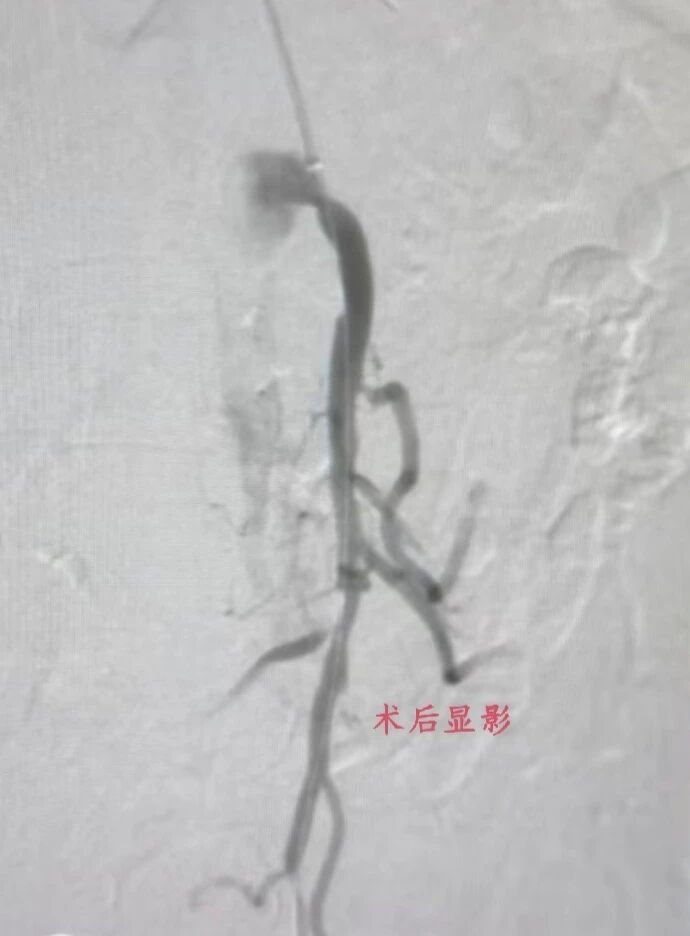

时间就是生命,鉴于患者高龄、基础病多,因传统开腹手术创伤大、风险高,术后并发症多,恢复时间较长。血管外科团队反复评估病情,与家属充分沟通后,决定采用微创介入手术治疗。科室迅速启动急诊手术绿色通道。术中,发现患者肠系膜上动脉起始处、距起始12cm处重度狭窄,15cm处完全闭塞,双侧肾动脉也有不同程度狭窄。随后,血管外科团队采用外周斑块切除系统清除肠系膜远端血栓,对重度狭窄处球囊扩张,操作精准、高效。术后造影显示,患者肠系膜上动脉管腔明显改善,血流量显著增加,无造影剂渗漏,手术成功,患者安返病房。

术后经过医护人员精心的治疗护理,患者腹部疼痛消失,饮食逐步过渡至正常饮食,生命体征平稳,目前该患者已痊愈出院。此次高龄复杂肠系膜上动脉栓塞患者的成功救治,是血管外科在急危重症血管疾病微创治疗领域的又一次成功实践,不仅考验了科室医生的临床诊断能力和手术操作水平,也体现了医院多学科协作的高效性。科室自成立以来,在庄百溪主任的指导下,不断攻克高难度血管外科手术,微创介入技术日益成熟,为众多血管疾病患者,尤其是高龄、基础病复杂的高危患者提供了安全、有效的治疗方案。未来,科室将继续深耕血管外科领域,以更精湛的技术、更优质的服务,为全疆患者的血管健康保驾护航。